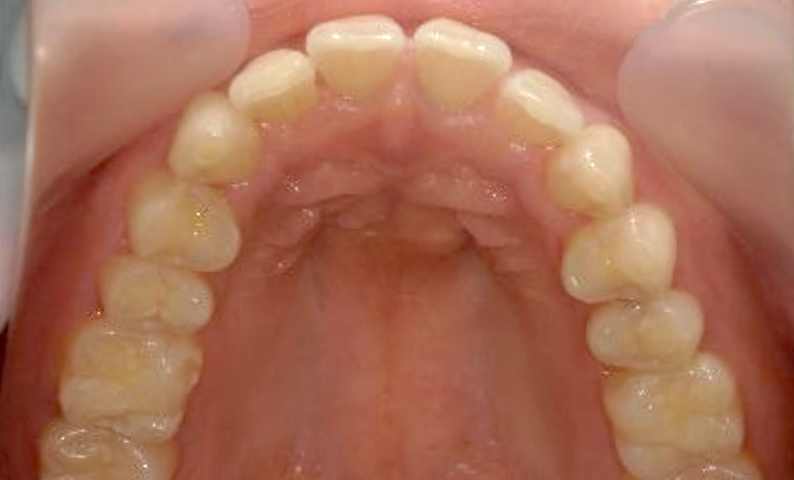

| 治療前 | 治療後 |

|---|---|

|